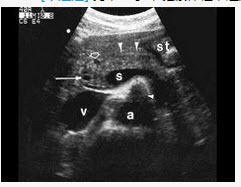

男,27岁,健康体检,超声图中箭头所指为()A: 肠系膜上动脉B: 肠系膜上静脉C: 胆总管D: 肝动脉E: 门静脉

男,27岁,健康体检,超声图中箭头所指为()

- A: 肠系膜上动脉

- B: 肠系膜上静脉

- C: 胆总管

- D: 肝动脉

- E: 门静脉